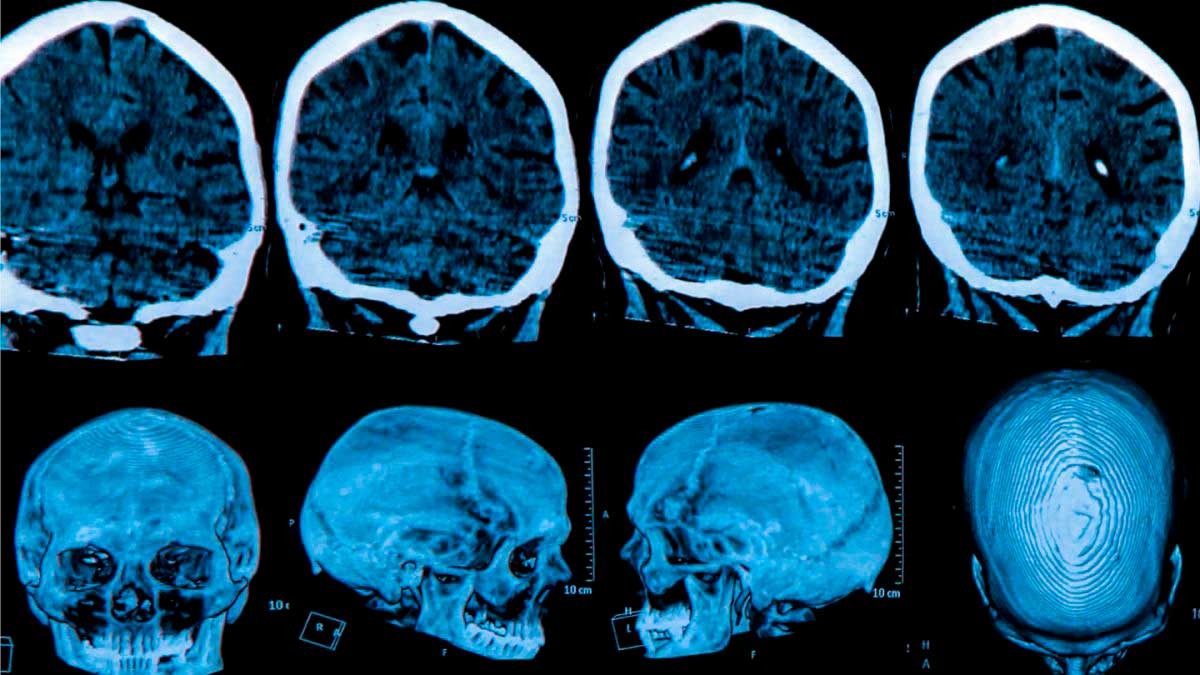

• Tomografía Axial Computarizada

Es la prueba idónea para ver el estado de los ganglios basales, especialmente del caudado y el putamen.